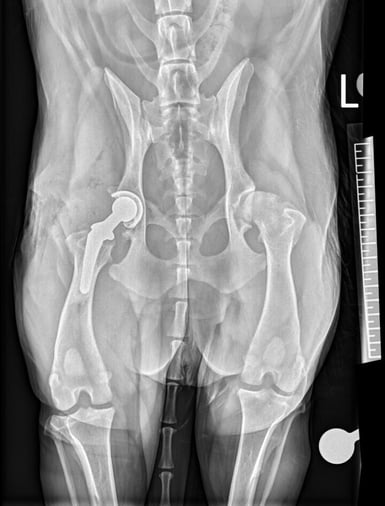

The final metal femoral head was placed and hip reduction was achieved with a good range of motion and stability. Standard layered soft tissue closure was performed after generous saline lavage of the surgical site. Radiographs were then taken post-operatively to assess the implant placement, which was correct, and a good cement mantle could also be seen (Figure 2A and 2B).